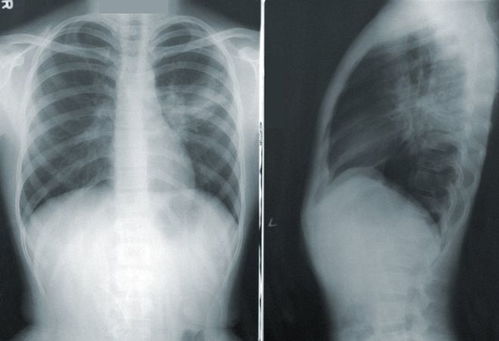

值得注意的是,舌根癌早期容易与普通口腔炎症混淆。如果上述症状持续两周以上或呈现进行性加重的趋势,建议尽早就医进行喉镜或活检检查。像歌手张咪的病例一样,任何反复的口腔病变都应当引起我们的警惕,及时排查风险,以免耽误治疗。